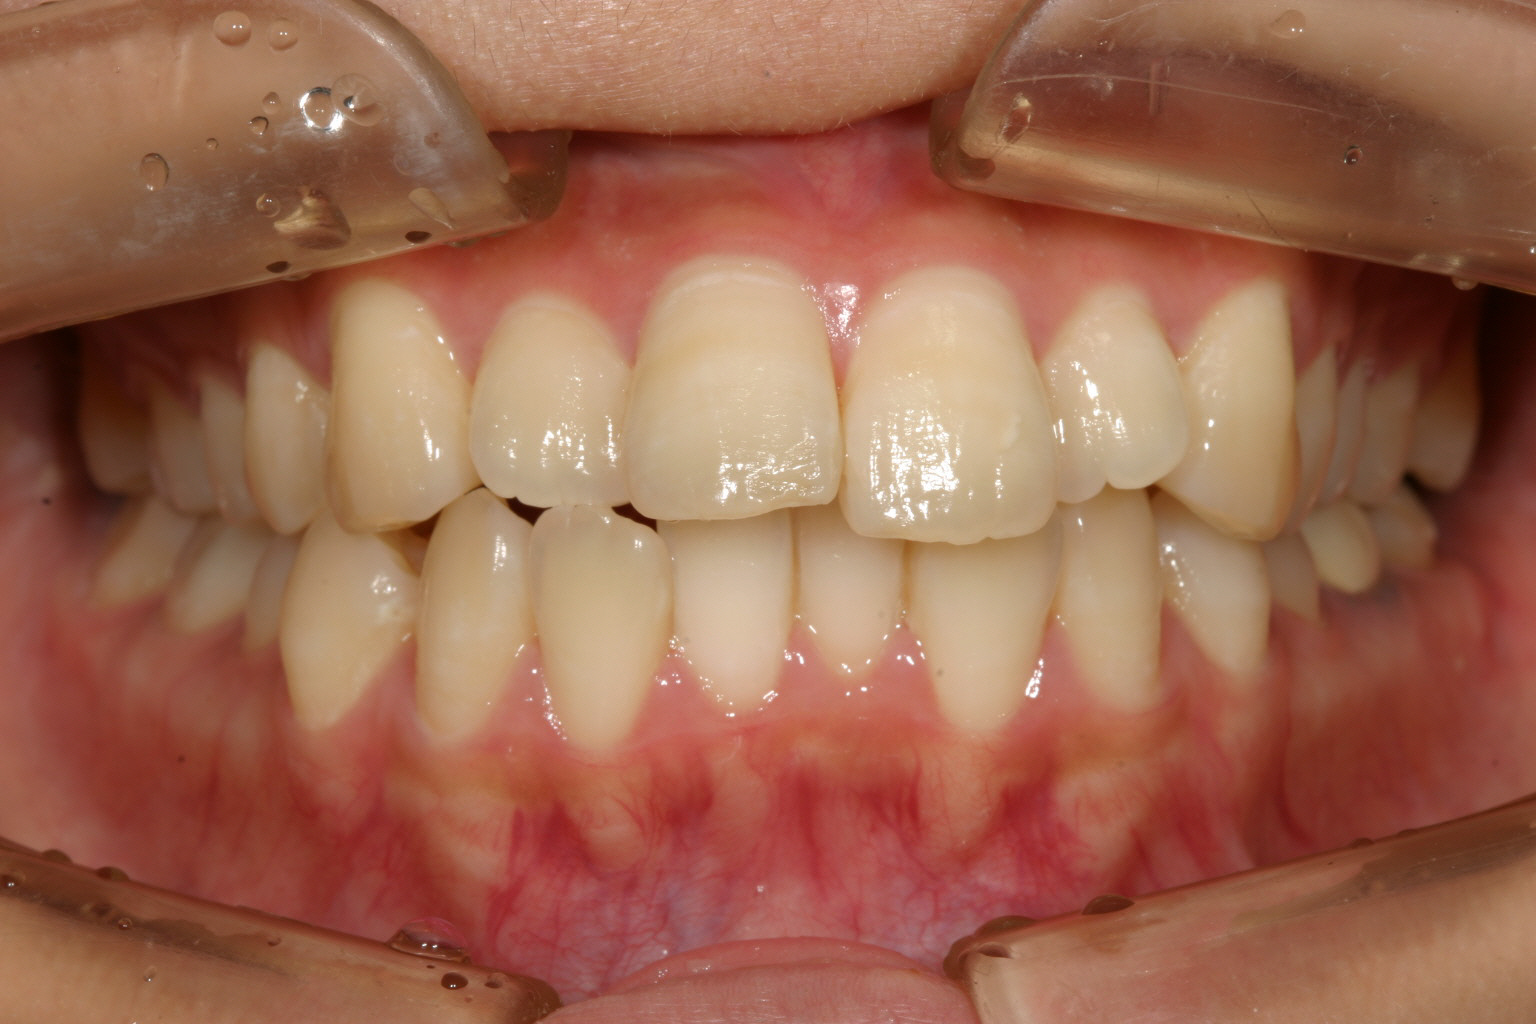

アーチか狭く前歯部が飛び出しています。

下顎もアーチが狭い為その付けが前歯にきて叢生になっています。

上下ともかなり飛び出しています。